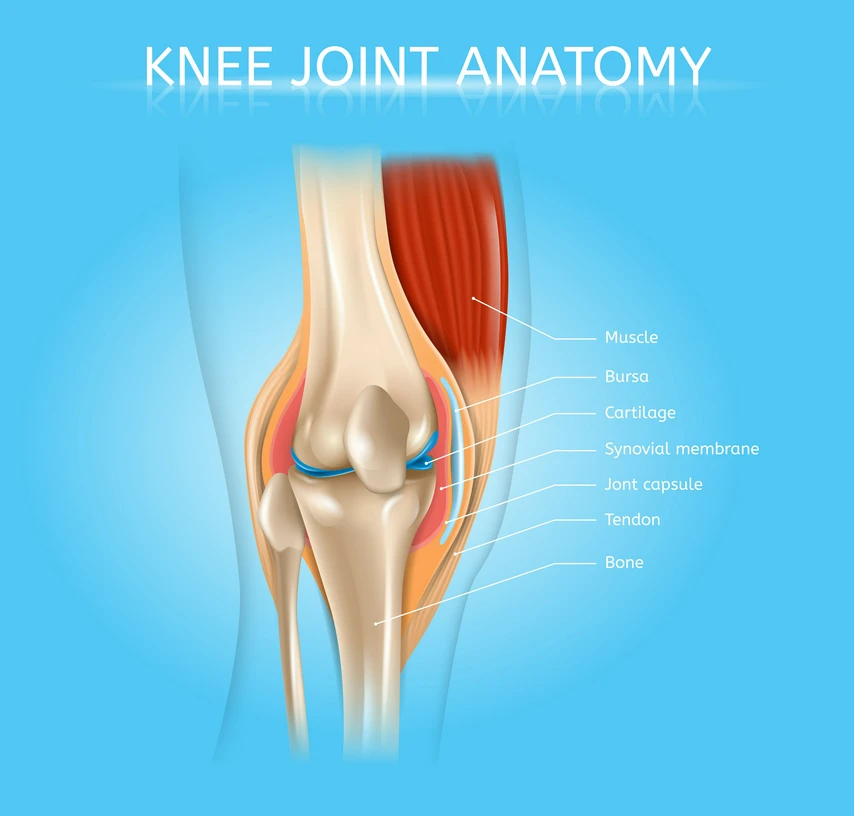

Comprising bones, muscles, cartilage, tendons, ligaments, and other connective tissues, it works in harmony to provide stability, facilitate movement, and safeguard vital organs.

The musculoskeletal system is a complex organ system that provides humans with the ability to move, support their body, and protect vital organs. It consists of bones, muscles, cartilage, tendons, ligaments, and other connective tissues.

Bones - Bones provide structural support, protect internal organs, and facilitate movement by serving as points of attachment for muscles. Bones are composed of a hard outer layer (cortical bone) and a spongy inner layer (trabecular bone) that contains bone marrow, where blood cells are produced.

Muscles - Muscles are responsible for producing movement by contracting and relaxing. They also help maintain posture and generate heat to keep the body warm. There are three types of muscles—skeletal (voluntary muscles that move bones), smooth (involuntary muscles found in organs), and cardiac (muscle of the heart).

Cartilage - Cartilage is a flexible, rubbery connective tissue that provides cushioning and support at joints. It reduces friction between bones and absorbs shock.

Tendons - Tendons are strong, fibrous connective tissues that attach muscles to bones, allowing the transfer of force from muscle contraction to bone movement.

Ligaments - Ligaments connect bones to other bones at joints, providing stability and limiting excessive movement. Like tendons, ligaments are made of dense collagen fibres, making them strong and resilient.

Bursae - Small fluid-filled sacs that reduce friction between moving parts in the body's joints.